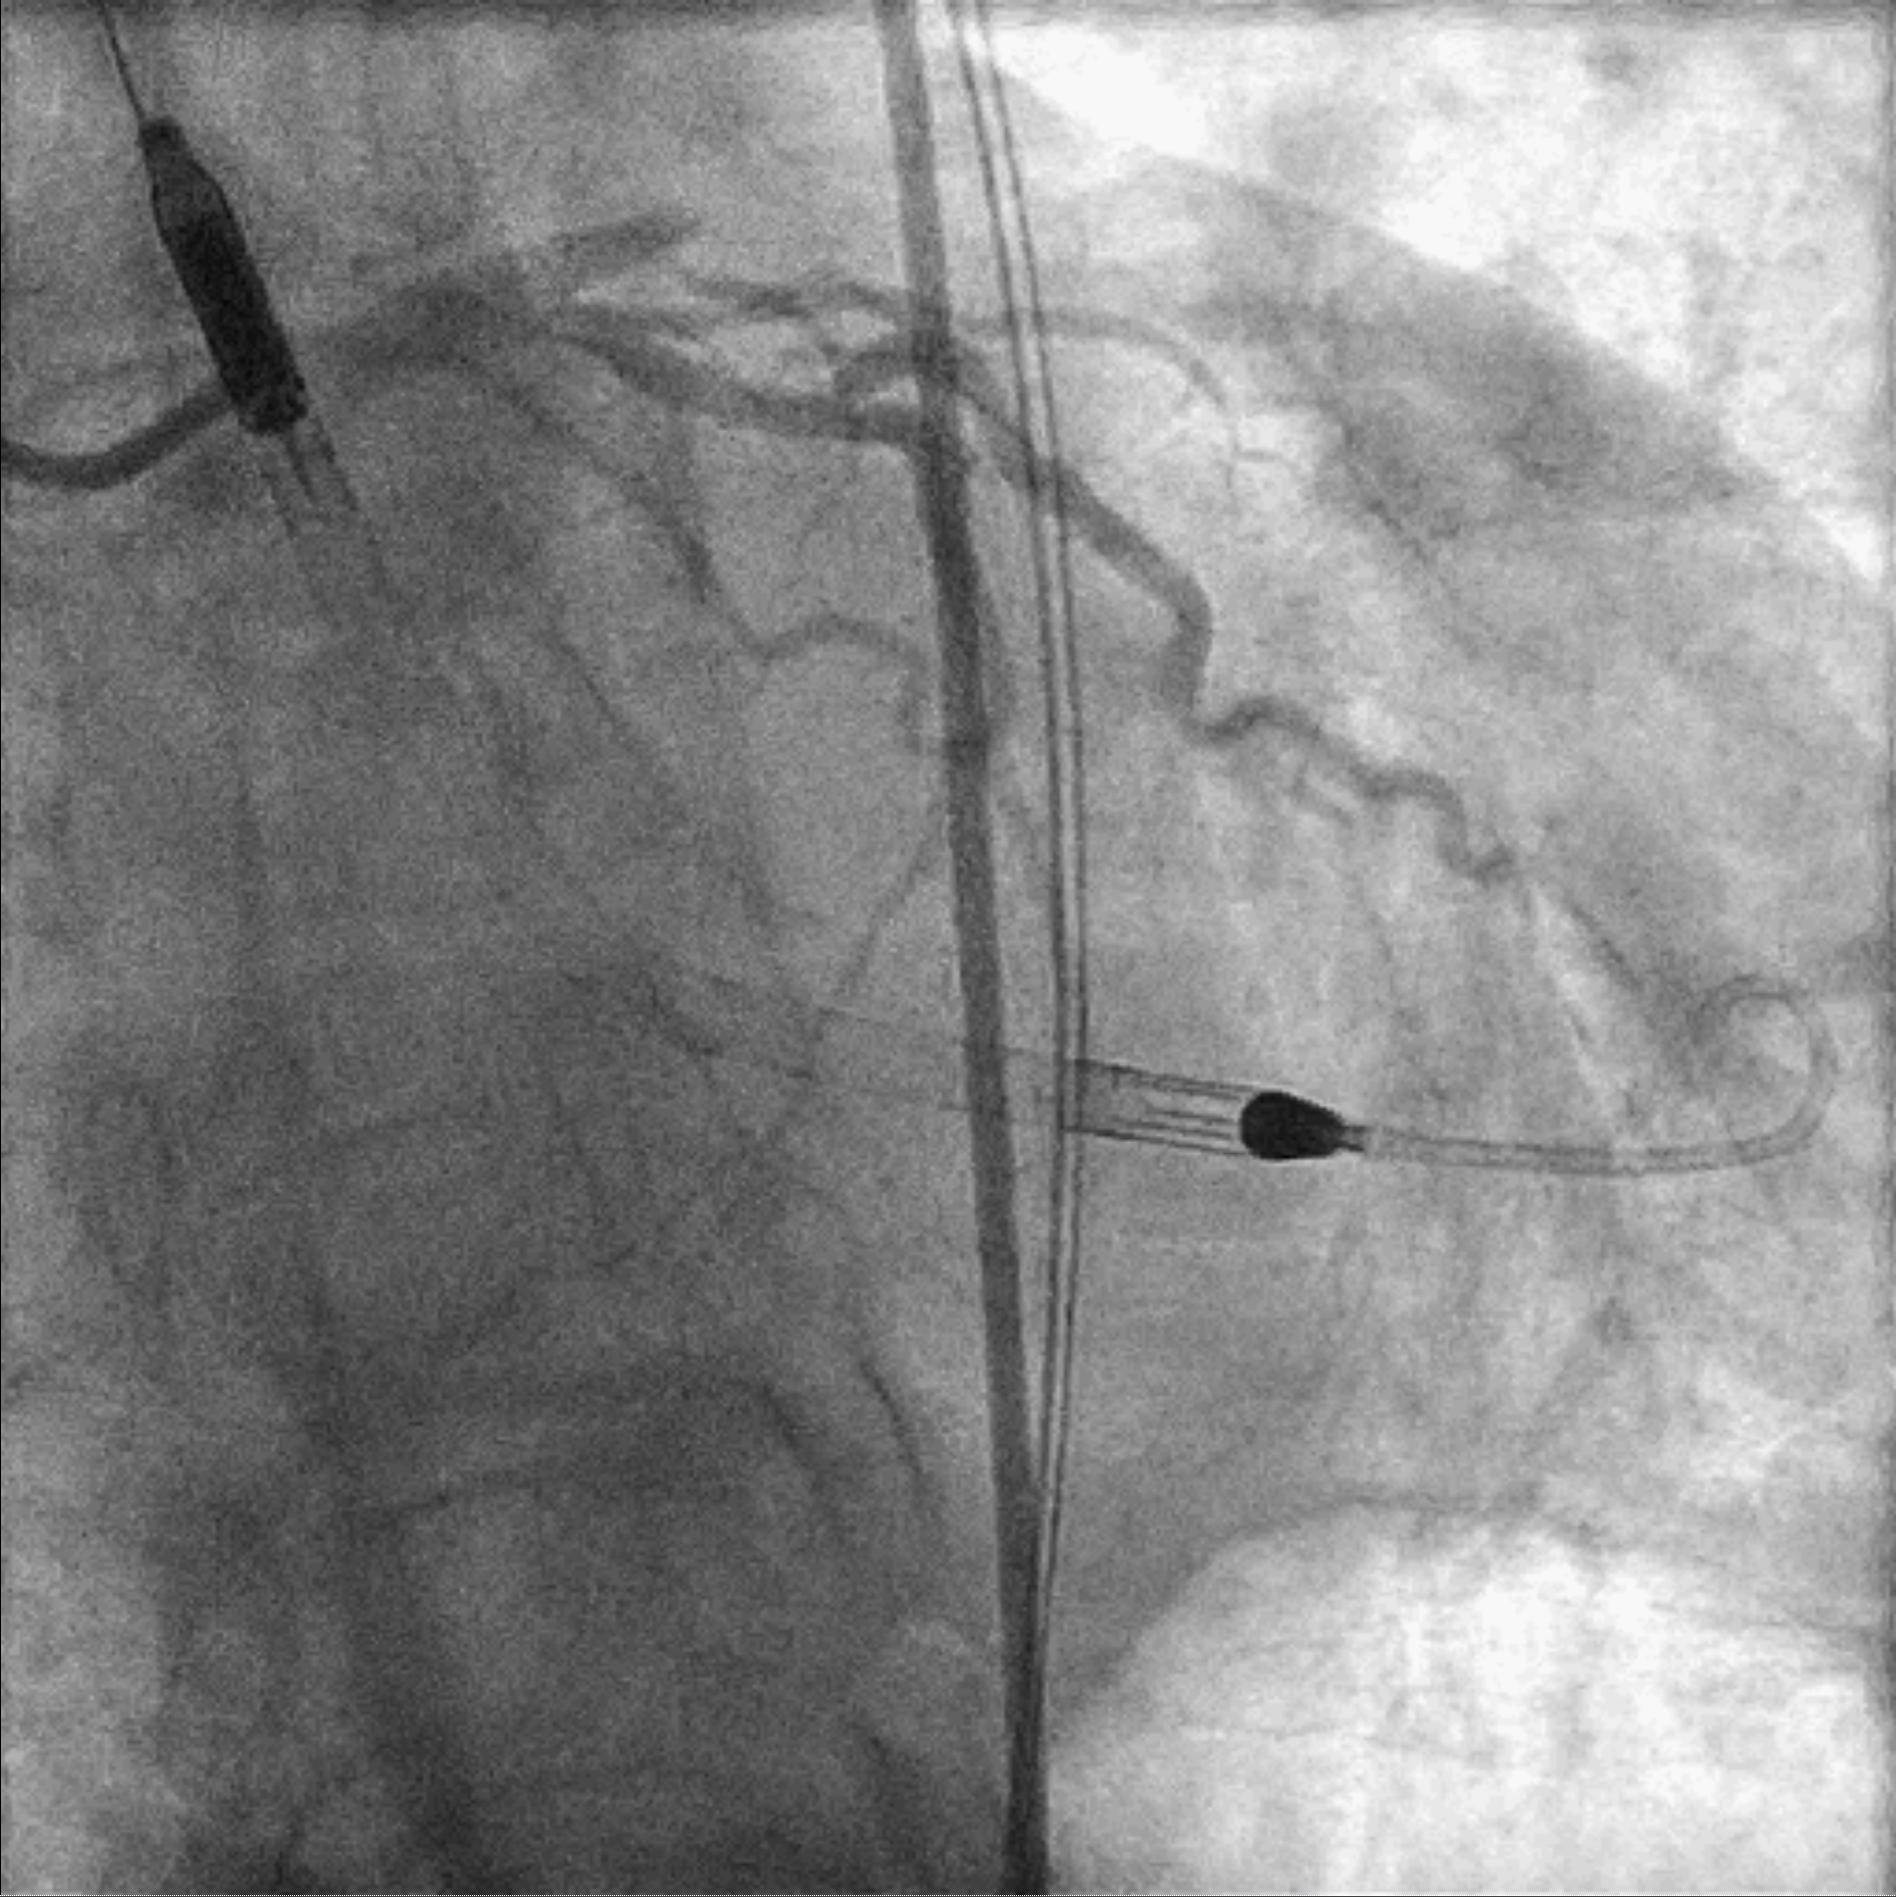

EBU 3.5 7Fr was used to engage left main common artery. Proximal LAD lesion was crossed with a Corsair Pro XS supported Fielder XT-R. Dottering with Sapphire 2.0/15 was unable to achieve flow in LAD. Low pressure inflation of 2.0 mm x 15 mm semi-compliant balloon at ostial to proximal LAD restored TIMI II flow. IVUS demonstrated organised clot in pLAD and plaque extension into LM. A 3.5 mm x 48 mm DES was deployed over mid-LM to mLAD at nominal pressure. The stent was further optimized with 5.0 mm x 6 mm and 4.0 mm x 15 mm non-compliant balloons under IVUS guidance. Intracoronary Adenosine was administered to improve coronary flow. Final angiogram showed TIMI III flow with no immediate complications. Faint retrograde flow to distal RCA was observed. A brief attempt to open RCA was made as the chronicity of the lesion was uncertain. However, Fielder XT-A supported by Corsair Pro XS failed to cross the lesion and the procedure was aborted.